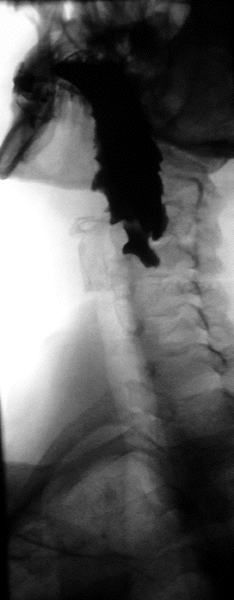

The simple barium swallow will normally reveal the diverticulum. It may also be found with upper GI endoscopy, or CT with oral contrast.